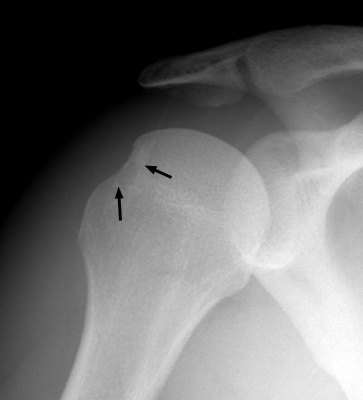

Diagnosis:s/p anterior shoulder dislocation Discussion:Frontal film of the right shoulder which reveals a defect of the posterolateral aspect of the humeral head, consistent with a Hill-Sachs deformity. The Hill-Sachs sign represents deformity of the superior, posterior border of the humeral head and is typically a result of impaction of the anterior inferior surface of the glenoid labrum on the posterolateral aspect of the humeral head during dislocation. References: